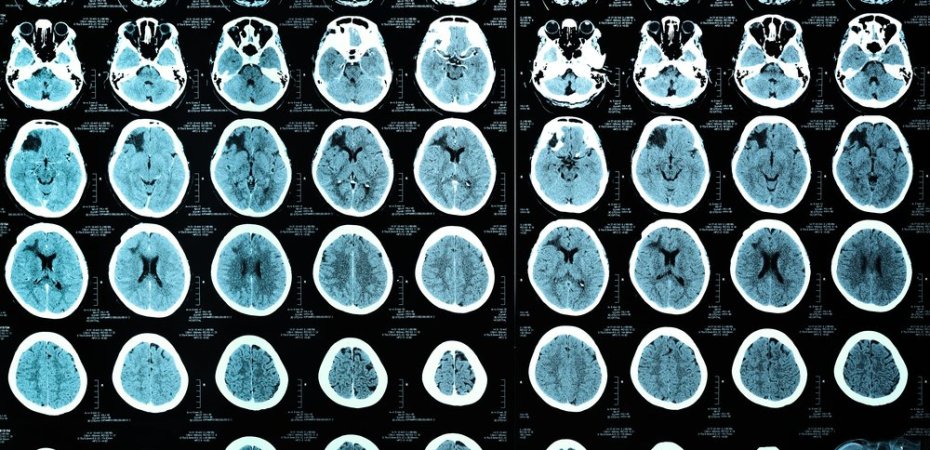

“I think the challenge lies in that this is a functional injury and not a structural injury,” Teena Shetty, a neurologist at the Hospital for Special Surgery in New York, told SportTechie. “Therefore a routine MRI is normal, but the patient is functionally impaired. That makes it more difficult to create a tool which can be administered both quickly and objectively on the sideline and have prognostic value.”